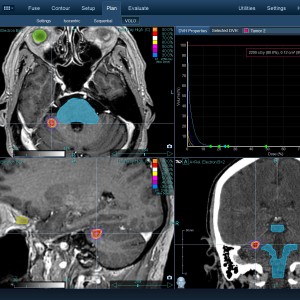

Στις παρακάτω φωτογραφίες θα δείτε παραδείγματα πλάνων θεραπείας καρκινικών όγκων με CyberKnife. Παρατηρήστε πόσο κοντά στους υγιείς ιστούς βρίσκονται οι καρκινικοί όγκοι που χρειάζεται να ακτινοβοληθούν. Μόνο με το CyberKnife και το προσωπικό πλάνο θεραπείας, μπορούν να ακτινοβοληθούν οι όγκοι χωρίς να πληγούν οι παρακείμενοι υγιείς ιστοί.

Μόνο με το CyberKnife και την κατάλληλη σχεδίαση της θεραπείας από έμπειρο νευροχειρουργό, μπορεί να ακτινοβοληθούν οι όγκοι χωρίς να επηρεαστούν από την ακτινοβολία οι υγιείς ιστοί. Αυτό εξασφαλίζει τη μέγιστη δυνατή απόδοση της ακτινοχειρουργικής θεραπείας των όγκων.

Ο νευροχειρουργός Λέκας Λεωνίδας έχει τη μεγαλύτερη εμπειρία στην Ελλάδα στο σχεδιασμό θεραπειών στερεοτακτικής ακτινοχειρουργικής όγκων του εγκεφάλου και του νευρικού συστήματος σε CyberKnife. Ο σχεδιασμός του πλάνου θεραπείας προϋποθέτει άριστη γνώση της ανατομίας και της απεικόνισης του κεντρικού νευρικού συστήματος έτσι ώστε να επιτευχθεί το βέλτιστο θεραπευτικό αποτέλεσμα με τη μέγιστη δυνατή προστασία των ευαίσθητων δομών.

Με κόκκινο χρώμα περιγράφεται η περιοχή του όγκου.

Με μπλε, κίτρινο και πράσινο χρώμα περιγράφονται οι υγιείς ιστοί που δεν πρέπει να ακτινοβοληθούν.

Παρατηρήστε πόσο κοντά βρίσκεται ο όγκος με τους υγιείς ιστούς.

Παρατηρήστε τις πάρα πολλές δέσμες του CynerKnife που ακτινοβολούν τους όγκους από διαφορετικές γωνίες ώστε να μην προσβληθούν από την ακτινοβολία οι υγιείς ιστούς.